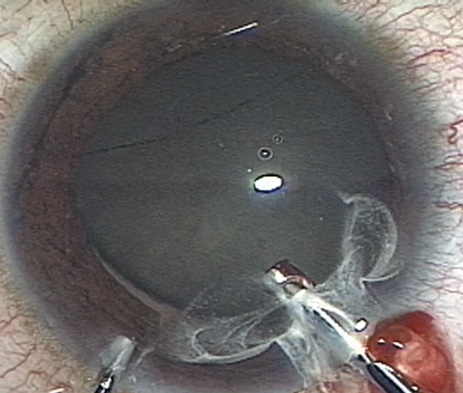

Fig. 10. The capsulorrhexis tear is more easily redirected by folding the capsule over, in advance of the tear.

Capsulorrhexis can be performed with a cystitome, capsulorrhexis forceps, or combination-type instruments. Regardless of which instrument is used, several principles can help the surgeon successfully complete capsulorrhexis. It is important to maintain the anterior chamber, because making the chamber shallow increases tension on the zonules and causes the tear to run peripherally. The authors recommend the use of a viscoelastic agent for maintaining chamber depth and, of course, for endothelial protection. Therefore, if the tear begins to run peripherally, the surgeon should redeepen the anterior chamber before attempting to redirect the tear. Additionally, folding the capsule margin can aid the surgeon in redirecting the tear more accurately (Fig. 10).